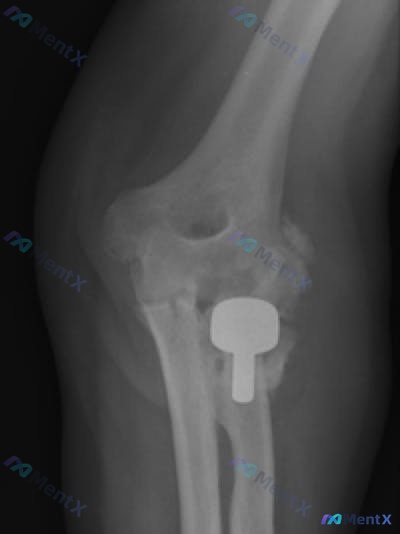

整理到一份左侧肘关节术后的影像资料,先把核心信息放出来,大家第一眼会怎么考虑? 背景:左侧肱骨远端骨折术后,复查侧位X光片(标记“L”)。 影像核心所见: 1. 肱骨远端可见金属接骨板+数枚螺钉内固定,钢板位置尚可,未见明显断裂/螺钉松动,可见骨愈合区域; 2. 肱尺、肱桡关节对位尚可,关节间隙无明...